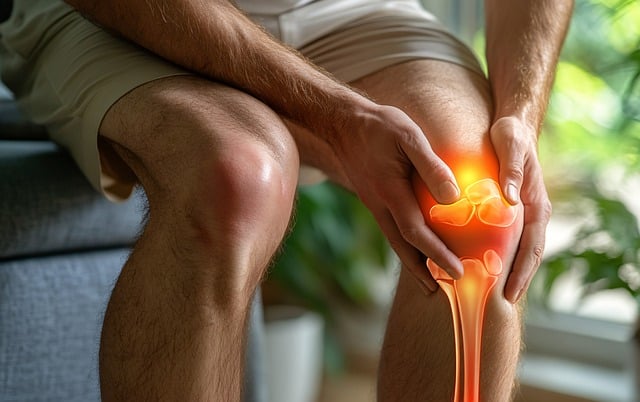

👉 손목, 발가락, 무릎 등 다양한 관절에서 통증 발생

👉 대칭적으로 양측 관절에 염증이 나타날 가능성이 큼

👉 아침에 30분 이상 지속되는 관절의 뻣뻣함